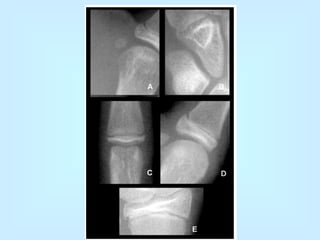

• Encaje-reciproco: • Siendo las superficies articulares una cóncava y otra convexa, se oponen una a la otra. Ejemplo: articulación esterno-clavicular, Trapecio-metacarpiana y calcáneo-cuboidea. • Trocleartrosis: Una de las superficies parece una polea.  Ejemplos: articulación del codo, las interfalangicas de las manos y pies, en la rodilla y la tibiotarsiana.

• Trocoidartrosis: Las superficies articulares siendo una cóncava y la otra convexa, forman un cilindro al estar unidas.  Ejemplo: articulación atloido-odontoidea y las radiocubitales superior e inferior.

• Encaje-reciproco: •Siendo las superficies articulares una cóncava y otra convexa, se oponen una a la otra. Ejemplo: articulación esterno-clavicular, Trapecio-metacarpiana y calcáneo-cuboidea. • Trocleartrosis: Una de las superficies parece una polea. Ejemplos: articulación del codo, las interfalangicas de las manos y pies, en la rodilla y la tibiotarsiana.

• Trocoidartrosis: Lassuperficies articulares siendo una cóncava y la otra convexa, forman un cilindro al estar unidas. Ejemplo: articulación atloido-odontoidea y las radiocubitales superior e inferior.